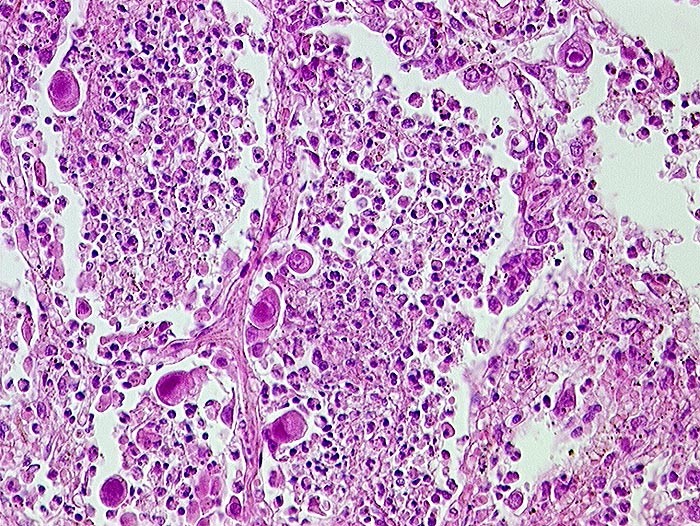

PathoPic – image database / PathoPic ID 218 - CMV (Zytomegalie) Pneumonie und Bronchopneumonie

CMV (Zytomegalie) Pneumonie und Bronchopneumonie

Virale Kerneinschlüsse mit Halo in Pneumozyten (sogenannte Eulenaugenzellen). Intraalveoläre Granulozyten bei zusätzlicher bakterieller Pneumonie.

HIV positiv seit 5 Jahren. Nachweis von zytomegalen Zellen im Hirn, in der Lunge, im Gastrointestinaltrakt, den Nieren und der Nebenniere. Zusätzlich bakterielle Pneumonie.